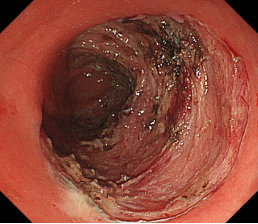

直肠巨大侧向发育型肿瘤,内镜下完整切除(ESD),术后病理证实粘膜内癌,不需追加治疗,达到治愈目的,保留正常器官,避免外科手术。